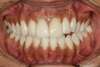

Il s'agit d'un cas d'une chute avec expulsion de l'incisive centrale droite et fracture de l'incisive centrale gauche.

Un implant avec greffe osseuse a été posé en site de l'incisive droite et une facette sur dent dévitalisée sur l'incisive gauche.

La réalisation a été faite par un laboratoire meilleur ouvrier de France.